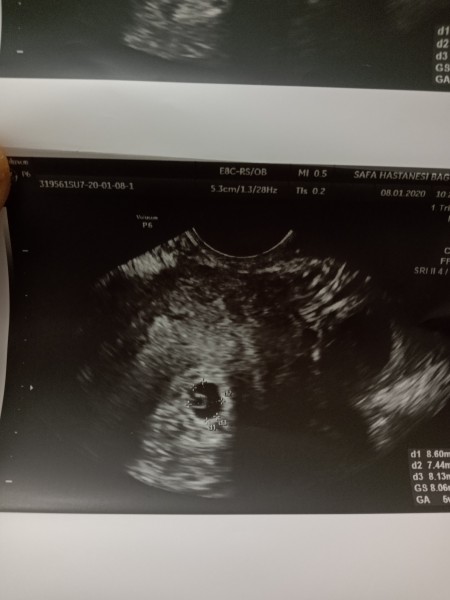

Kese Var Yolk Kesesi Var Ama Icinde Bebek Yok Kadinlar Kulubu

Yolk Sac Kesesini Goruyormusunuz Lutfen Yardim Kadinlar Kulubu

Yolk Kesesi Olup Bebek Olmayanlar Kadinlar Kulubu